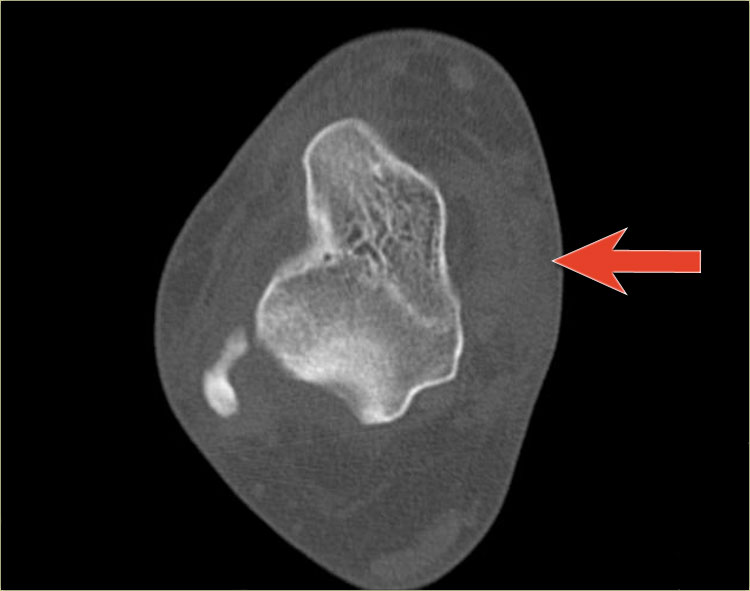

Đây cũng là gãy xương Salter-Harris type III.

Lưu ý rằng đồng thời có gãy xương Tillaux.

Chúng ta sẽ thảo luận về các gãy xương này ở phần tiếp theo.